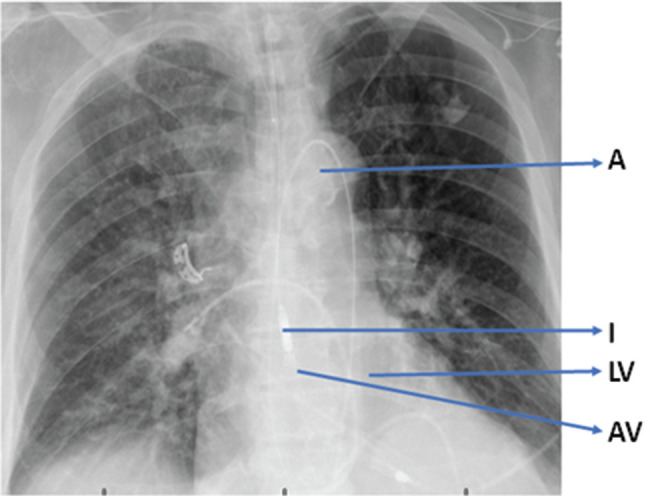

High-risk cardiac patients undergoing complex electrophysiology procedures face potential hemodynamic instability, necessitating effective mechanical circulatory support. The catheter-based Impella® ventricular assist device (Abiomed, Danvers, MA, USA) is crucial to stabilizing hemodynamics by improving the flow of blood from the left ventricle to the aorta. Its automated controller ensures cerebral hemodynamic stability, allowing for bedside adjustments. Herein, we present a case series illustrating the versatility of the Impella® device in managing patients during complex electrophysiology procedures and highlighting its role in mitigating hemodynamic compromise.